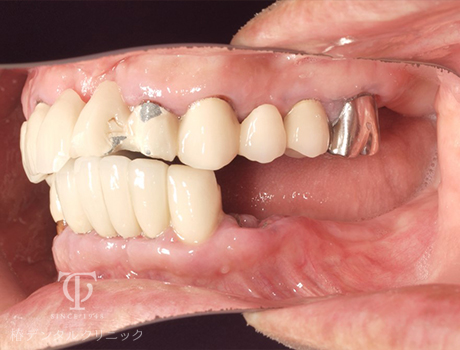

術前

術後の上顎内冠

術後の上顎AGCテレスコープ義歯

- 症状

- 右上の痛み

- 治療期間

- 約1年半

- 治療費用

- (上顎)インプラント治療:473,000円×2

(上顎)AGCテレスコープ義歯:1,500,000円

(下顎)インプラント治療:473,000円×2

右上の歯が痛いということで来院されました。インプラントとAGCテレスコープという方法でかみ合わせを再構築しました。

【リスク・副作用】

インプラント治療後、痛みや違和感、出血、腫れなどが出る事があります。喫煙者、糖尿病などの方の場合、歯が生着しない場合があります。入れ歯を清潔に保たないと虫歯や歯肉炎、歯周病になるリスクがあります。